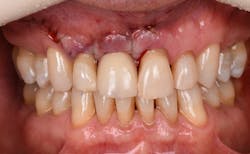

Figure 12: Pre-op clinical photo shows the discrepancies and disharmony of the gingival height. Incisions for esthetic crown lengthening on tooth No. 9 were done via the Er:YAG laser in contact mode (20 pps/60 mJ) to remove excess soft tissue in accordance with the pre-op probing depth measurements.

Figure 13: Exposure of the bony tissues via a full-thickness flap shows osseous irregularities and exostosis ledges that are contributing to the gingival discrepancy. Calculus can be observed attached to the root surface of the teeth.

Figure 14: After osseous shaping and recontouring was done using the Er:YAG laser in contact mode (20 pps/80 mJ). All bony ledges and crestal bone were removed on teeth Nos. 9–11.

Figure 15: Immediate post-op of tissues repositioned into place. Simple interrupted sutures were used.

Figure 16: Two-year post-op shows gingival health and maintenance of gingival tissues.